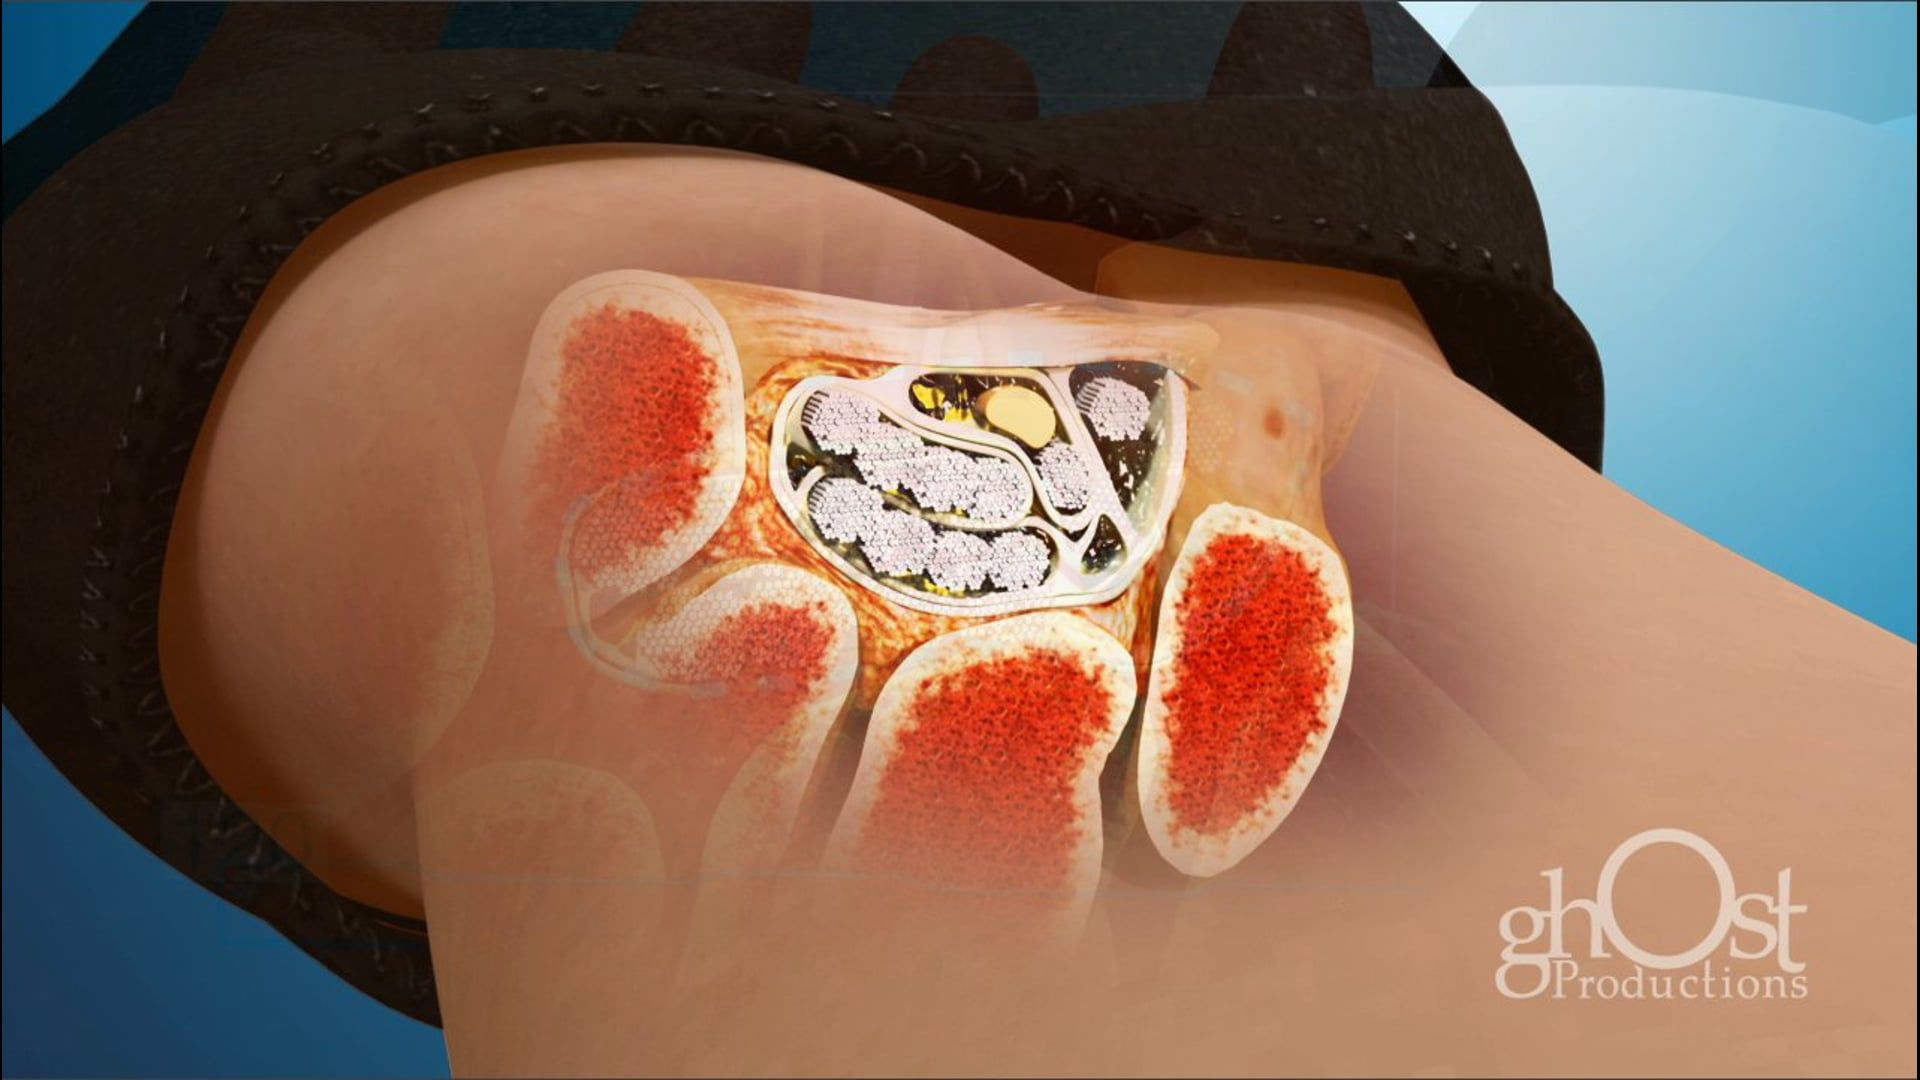

Ghost Productions' animation showcases the Keo Brace, a revolutionary device for Carpal Tunnel Syndrome treatment, providing support to the wrist and reducing pressure on the median nerve. Medically accurate and informative, it's a must-see for healthcare professionals and patients.

Ghost Productions has produced a visually stunning animation that highlights the Keo Brace, a revolutionary device used in the treatment of Carpal Tunnel Syndrome. This video showcases the Keo Brace's unique design and its ability to alleviate the symptoms of Carpal Tunnel Syndrome by providing support to the wrist and reducing pressure on the median nerve. The animation is medically accurate and provides a detailed explanation of how the Keo Brace works, making it an invaluable resource for healthcare professionals and patients alike. This video is a must-see for anyone interested in the latest advancements in the treatment of Carpal Tunnel Syndrome.

Keo Brace, Carpal Tunnel Syndrome, wrist support, median nerve, medical animation, healthcare professionals, patient education, medical device, treatment advancements